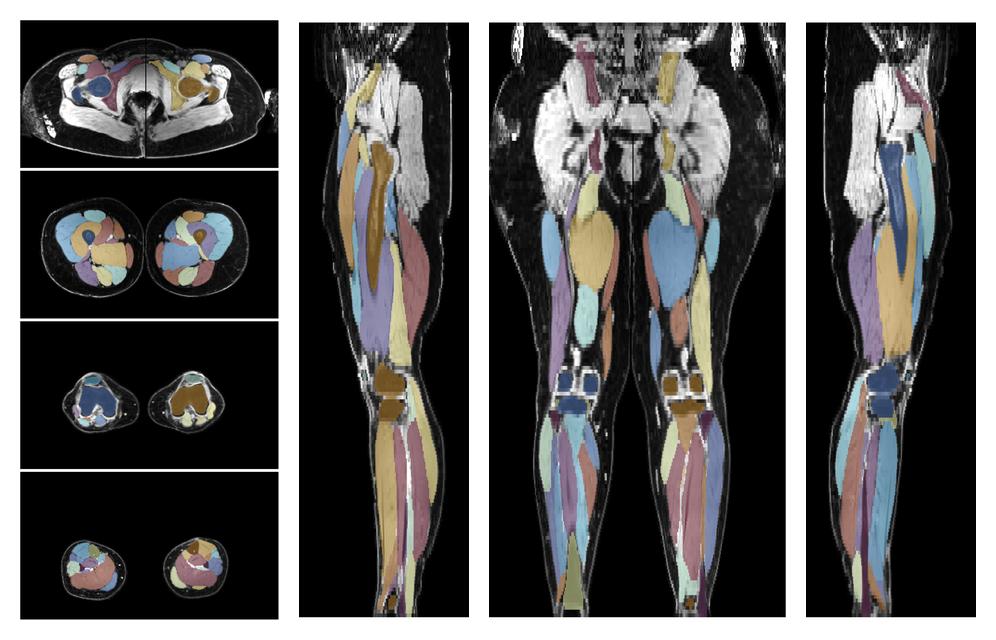

Muscle segmentation

Convolution neural network based (UNET) fiber automated muscle segmentation, for information look here».

• 3D volume render of automated muscle segmentation.

3D render of automated muscle segmentation labels generated using a CNN UNET.

• Automated muscle and bone segmentation.

Overlay of automated muscle segmentation labels on dixon water image.